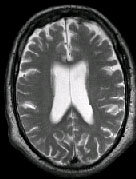

IMAGING FINDINGS: The CT was performed on AIC’s new 16-slice helical multi-slice CT (MSCT). Both routine single-slice and thin-section helical scans were obtained and 3D/Multiplanar images were performed on the Advanced 3D workstation. Fig. 1 shows an image at the level of the lateral ventricles with possible high density within the sulci on the right (arrow). To confirm this finding, an MRI with contrast was then obtained on AIC’s 1.5-Tesla high-field, short-bore Siemens MRI. Fig. 2a-b are T2-weighted images at the same level showing NO definite abnormality. T1-weighted images (not shown) were also negative. The post-contrast images (not shown) showed NO abnormal enhancement in this region, either. Diffusion-weighted images were also negative. However, Fig. 3a-b, which are FLAIR images, demonstrate clear hyperintensity within multiple sulci involving the right temporo-parietal area (arrows).

DIAGNOSIS: The FLAIR images are compatible with Subarachnoid disease. The Differential Diagnosis includes: (1) Subarachnoid Hemorrhage (SAH); (2) Meningitis; (3) Infarct; (4) Flow Artifact. Lack of enhancement is against meningitis. Acute infarct was ruled out on the basis of negative Diffusion MRI and lack of cytotoxic edema on the FLAIR images. Focal abnormality is against flow artifact (which is more diffuse and usually in the posterior fossa on FLAIR images). The clinical history of trauma and the high-density on CT and hyperintensity on FLAIR images within the sulci are diagnostic of Acute Post-traumatic Subarachnoid Hemorrhage (SAH).

DISCUSSION: MRI FLAIR imaging is the modality of choice for diagnosis of supratentorial SAH. In the posterior fossa, however, CT is superior due to flow artifacts on FLAIR images in the peripontine/ambient cisterns. A combination of CT and MRI would be ideal to optimize detection sensitivity.